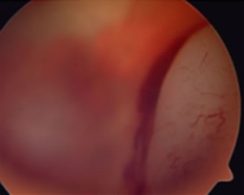

El exámen oftalmológico por parte del especialista es aconsejable realizarlo bajo anestesia general. El diagnóstico se logra mediante el exámen de fondo de ojo bajo dilatación pupilar. Durante el exámen se realizan dibujos de la retina y el/los tumores y se pueden sacar retinografías color digitales de la misma (fotos) que sirven para el seguimiento. Pueden ayudar al diagnóstico la ecografía ocular, la Tomografía Computada y la Resonancia Magnética Nuclear. No es necesario realizar biopsia para llegar al diagnóstico.

La mayoría de los casos son derivados al oftalmólogo por leucocoria, pupila blanca.

Estrabismo (ojos desviados) es la siguiente forma de presentación, y otras formas de presentación son más raras.